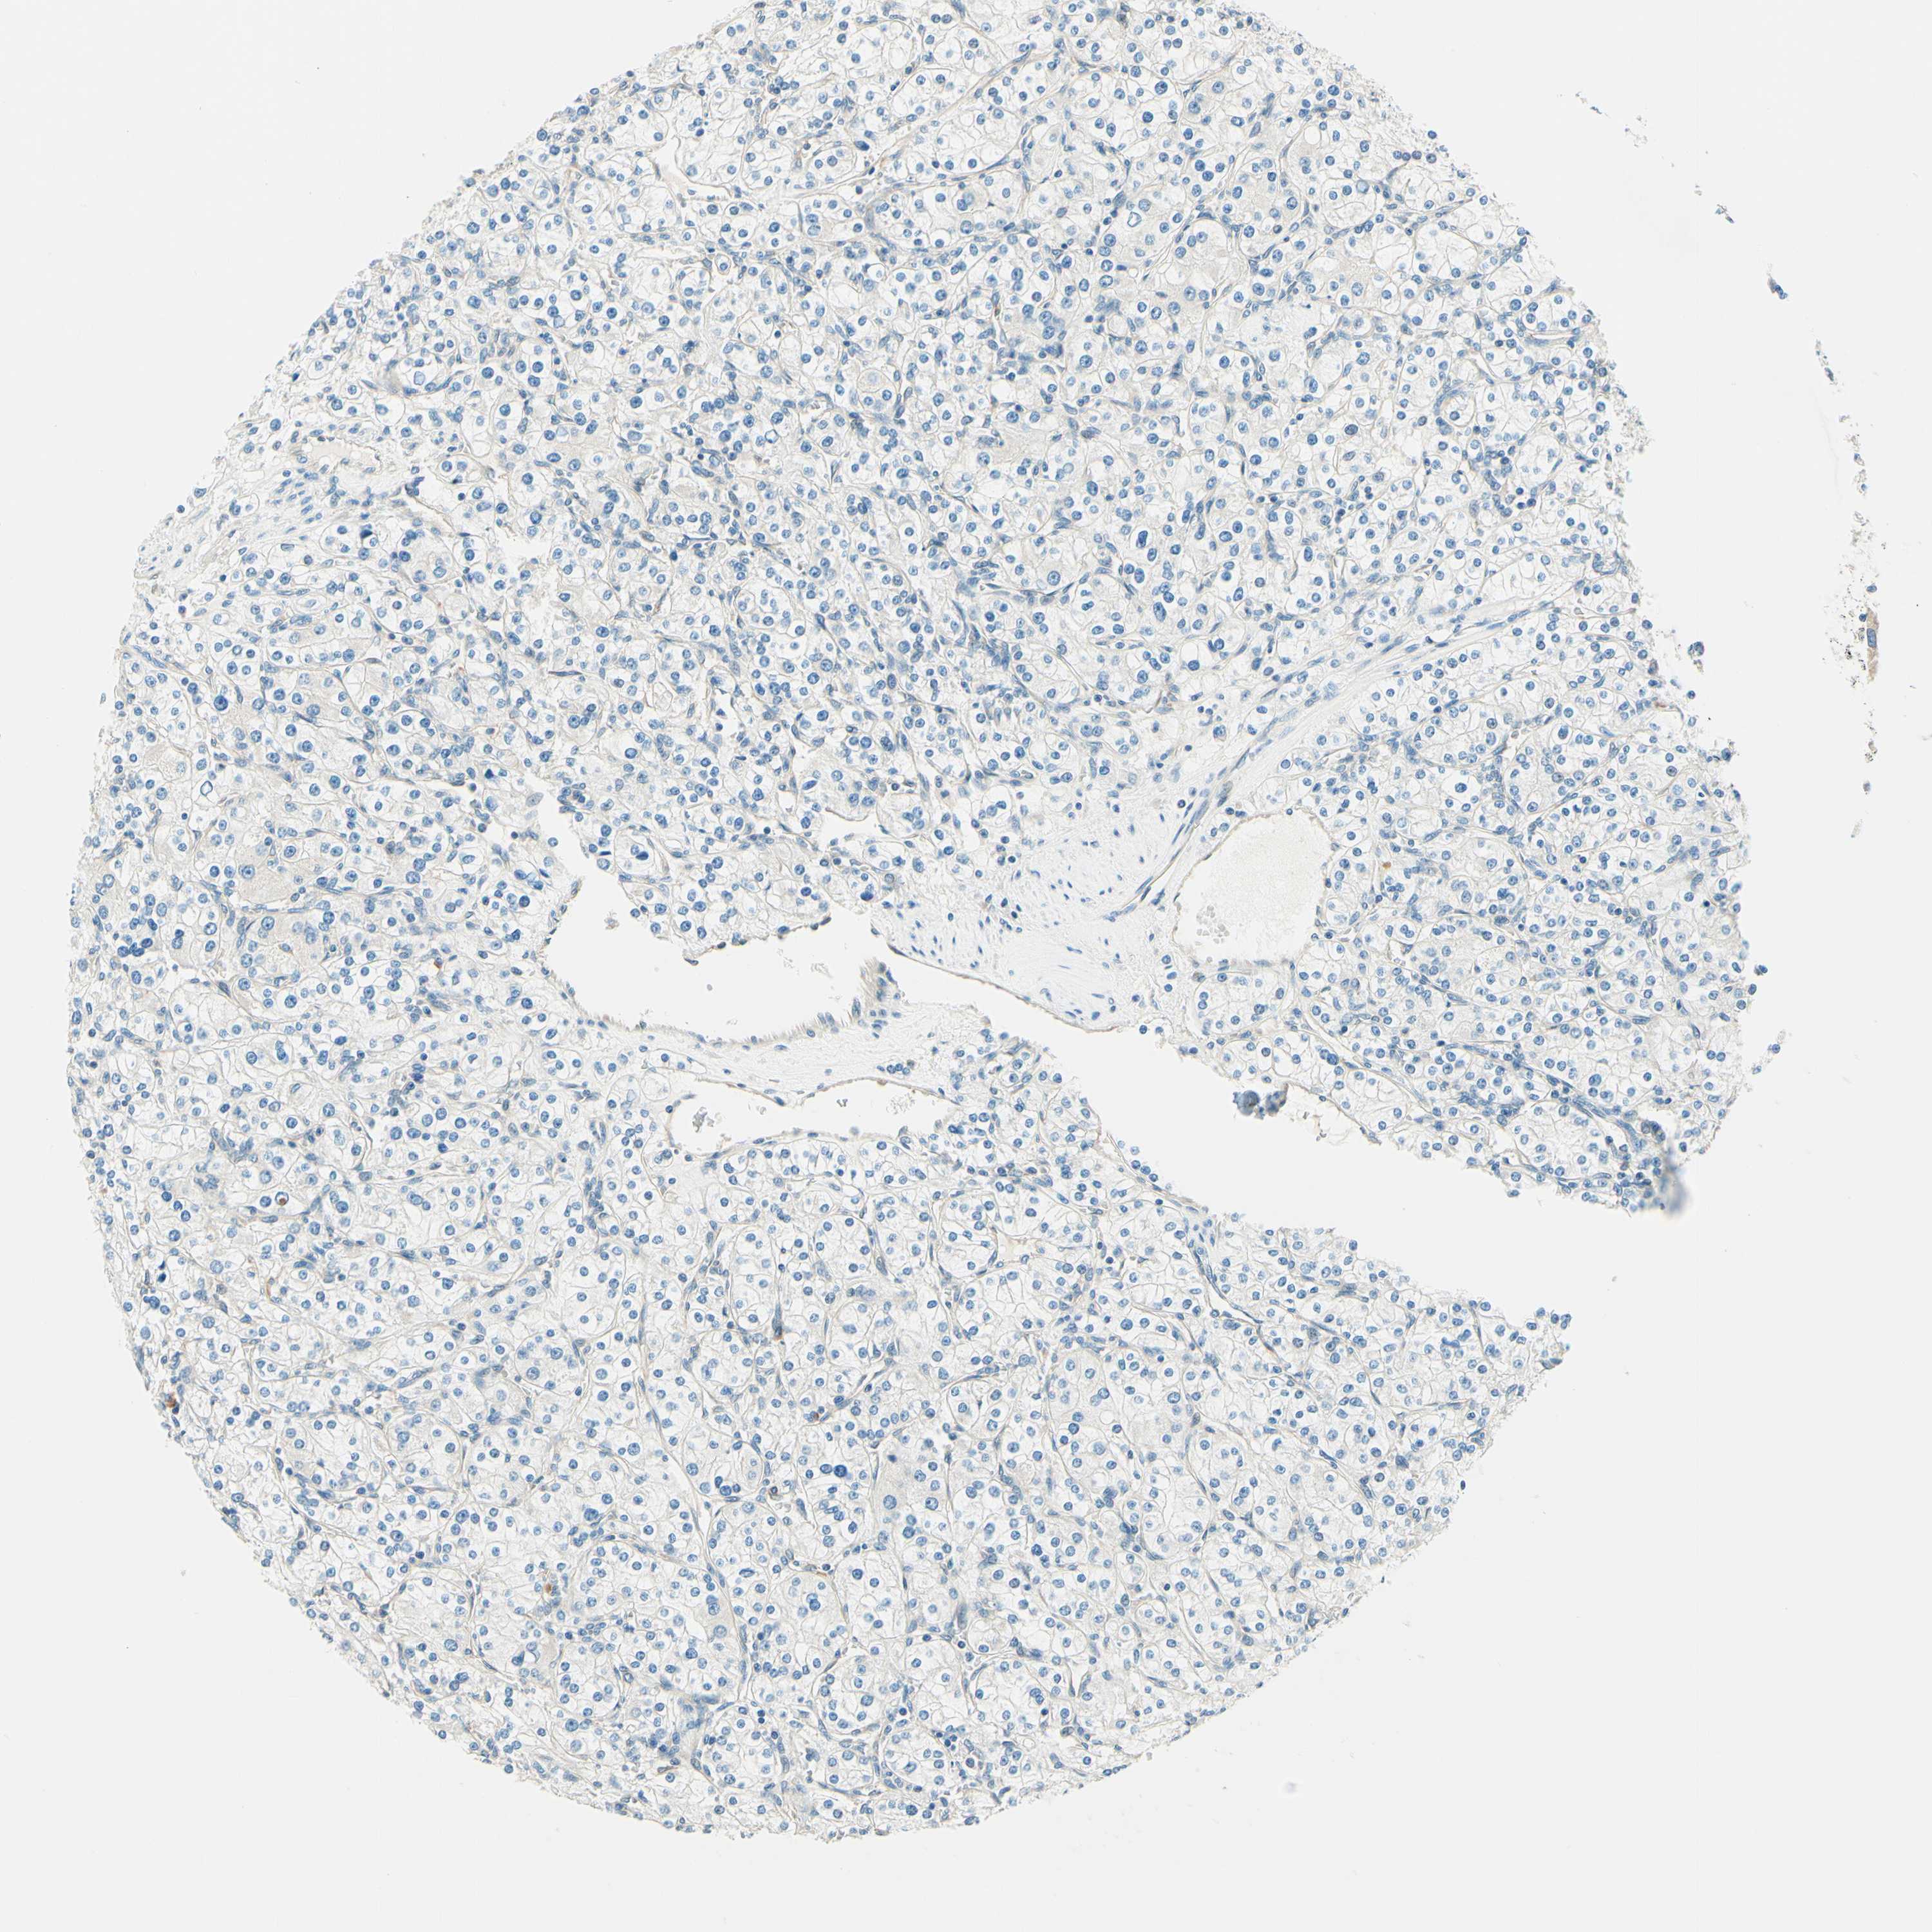

KIDNEY RENAL CLEAR CELL CARCINOMA (TCGA) - Interactive survival scatter ploti

The Survival Scatter plot shows the clinical status (i.e. dead or alive) for all individuals in the patient cohort, based on the same data that underlies the corresponding Kaplan-Meier plots. Patients that are alive at last time for follow-up are shown in blue and patients who have died during the study are shown in red.

The x-axis shows the expression levels (FPKM) of the investigated gene in the tumor tissue at the time of diagnosis. The y-axis shows the follow-up time after diagnosis (years). Both axes are complimented with kernel density curves demonstrating the data density over the axes. The top density plot shows the expression levels (FPKM) distribution among dead (red) and alive patients (blue). The right density plot shows the data density of the survived years of dead patients with high and low expression levels respectively, stratified using the cutoff indicated by the vertical dashed line through the Survival Scatter plot. This cutoff is automatically defined based on the FPKM cutoff that minimizes the p-score. The cutoff can be changed by dragging the vertical line or by entering a cutoff value in the square labeled "Current cut-off".

Under the Survival Scatter plot the p-score landscape (black curve; left axis) is shown together with dead median separation (red curve; right axis). Dead median separation is the difference in median mRNA expression between patients who have died with high and low expression, respectively. It is calculated as follows: median FPKM expression of dead patients with high expression - median FPKM expression of dead patients with low expression. This is intended to aid the user in visually exploring custom cutoffs and the associated p-scores and dead median separation.

Individual patient data is displayed and can be filtered by clicking on one or more of the category buttons on the top of the page. Categories describing expression level and patient information include: high, low, alive, dead, female, male and tumor stages. The scale of the x-axis can be toggled between linear and log-scale by clicking on the "x log" button. Mouse-over function shows TCGA ID, patient information and mRNA expression (FPKM) for each patient.

& Survival analysisi

Kaplan-Meier plots summarize results from analysis of correlation between mRNA expression level and patient survival. Patients were divided based on level of expression into one of the two groups "low" (under cut off) or "high" (over cut off). X-axis shows time for survival (years) and y-axis shows the probability of survival, where 1.0 corresponds to 100 percent.

TAOK2 is potential prognostic, high expression is favorable in Kidney Renal Clear Cell Carcinoma (TCGA)

: 26.09

TCGA RNA samplesi

RNA-seq data is reported as average FPKM (number Fragments Per Kilobase of exon per Million reads), generated by the The Cancer Genome Atlas (TCGA) .

Normal distribution across the dataset is visualized with box plots, shown as median and 25th and 75th percentiles. Points are displayed as outliers if they are above or below 1.5 times the interquartile range. FPKM values of the individual samples are presented next to the box plot.

Average pTPM 25.2

Number of samples 521